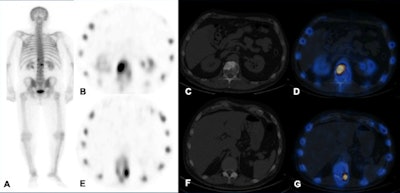

Like planar scintigraphy, SPECT uses gamma rays. Both these modalities are highly sensitive, widely available, and relatively cheap. Compared with planar scintigraphy, which has poor spatial resolution (1 cm), SPECT-CT can more accurately localize metabolically active foci and characterize them, reducing equivocal reports and allows reliable identification of degenerative disease, often difficult to be distinguished from bone metastasis on other modalities, they stated.

Technetium-99m (Tc-99m) MDP is a bone-specific SPECT and planar scintigraphy tracer. Increased uptake occurs in areas of osteoblastic reparative activity. The main pitfalls are the following:

- Reduced sensitivity to metastases isolated to the bone marrow, as these are usually osteolytic

- Flare response (increased radiotracer uptake that occurs early in the course of treatment) causes diagnostic confusion.

- Assessment of disease progression is limited to emergence of new lesions only. SPECT quantitation techniques are evolving and therefore cannot assess the progression/regression of pre-existing lesions accurately.

F-18 NaF is a bone-specific tracer. Uptake of F-18 NaF onto hydroxyapatite, the main inorganic component of bone, correlates with bone metabolism and vascularity. The main advantages are the following:

- Better pharmacokinetic characteristics

- High quality images because of high bone to soft tissue activity ratio

- Relatively short imaging time

- Provides quantitative assessment of bone metabolism

- Increased uptake in osteoblastic and mixed lesions that may not manifest as sclerosis on CT

On the flip side, high uptake in areas of elevated osteoblastic activity can also be present in some benign processes, detection of early bone marrow metastases is unclear, small predominant lytic metastases are more likely to be missed, and flare phenomenon results in difficulty assessing treatment response at the early stage, Wong and colleagues added.

Recent studies suggest F-18 NaF PET-CT is superior to Tc-99m MDP planar scintigraphy and SPECT, but comparable to diffusion-weighted MRI, in the detection of bone metastases in prostate cancer patients, the authors wrote.